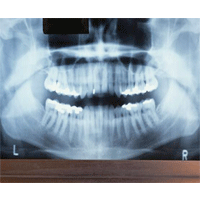

معاون پژوهشی دانشکده‌ی دندانپزشکی دانشگاه علوم پزشکی تهران از ساخت نخستین دستگاه ارزیابی ترک‌های مینایی دندان با استفاده از نرم افزار به همت پژوهشگران این دانشکده خبر داد.

به‌گزارش ایسنا، دکتر «محمد صادق احمد آخوندی» با اعلام این مطلب گفت: طرح ساخت این دستگاه طی یک سال و نیم گذشته انجام شده و در حال حاضر مراحل تکمیل نرم‌افزار و ثبت رسمی را می گذراند.

وی ادامه داد: این دستگاه قادر خواهد بود از طریق تصاویر داخل و خارج دهانی و انتقال آن به رایانه تصویر واضحی از سطح مینای دندان بردارد و طول و زاویه‌ی ترک را به دقت بررسی کند.

دکتر «آخوندی» با بیان این‌که دستگاه‌های قبلی تشخیص ترک‌های مینایی فقط قادر به بررسی ترک بوده‌اند، تصریح کرد: وجود نرم افزار در این طرح امکان استفاده از تصاویر خارج و داخل دهان و بررسی آن در رایانه را به کاربر می دهد. همچنین مقدار، زاویه و نوع ترک نیز مورد ارزیابی کامل قرار می گیرد.

این عضو هیأت علمی دانشکده‌ی دندانپزشکی دانشگاه علوم پزشکی تهران در پایان خاطرنشان کرد: این دستگاه به مرحلة‌ی بهره‌برداری رسیده است اما روند ثبت نهایی آن در داخل و خارج کشور هنوز ادامه دارد.